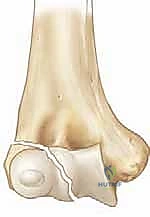

* الدرجة الثالثة (Stage 3): الكسر متحرك بالكامل، والقطعة المكسورة دارت حول نفسها بسبب شد العضلات، مما أدى لانخلاع جزئي في المفصل.

الجزء المكسور من اللقيمة الوحشية لا يظل ساكناً في مكانه كقطعة زجاج مكسورة، بل إنه يظل متصلاً بقوة بأنسجة رخوة وعضلات قوية:

1. عضلات باسطة الرسغ والأصابع (Extensor Musculature): تنشأ هذه العضلات من اللقيمة الوحشية. عند حدوث الكسر، تقوم هذه العضلات بشد القطعة المكسورة وسحبها للأسفل وللخلف.

بسبب هذه الانقباضات العضلية المستمرة، فإن كسر اللقيمة الوحشية يميل دائماً إلى "التباعد" و"الدوران" (Displacement and Rotation). هذا الشد العضلي هو السبب الرئيسي الذي يجعل علاج هذا الكسر بالجبس فقط أمراً مستحيلاً في معظم الحالات المتحركة، حيث تتطلب الحالة تثبيتاً ميكانيكياً (أسلاك معدنية) للتغلب على قوة العضلات. ومع ذلك، فإن هذه الاتصالات العضلية ضرورية جداً للحفاظ على إمداد الدم (Blood Supply) إلى القطعة المكسورة. الجراح الماهر يعرف كيف يرد الكسر دون تدمير هذه الأوعية الدموية الدقيقة.

الجراحة هي المعيار الذهبي والأكثر أماناً لأي كسر متحرك (أكثر من 2 ملم) أو الكسر الذي تعرض للدوران (Jakob Stage 2 & 3). الهدف من الجراحة هو إعادة القطعة المكسورة إلى مكانها بدقة ميكروسكوبية وتثبيتها بقوة لمنع حركة العضلات من إزاحتها مرة أخرى، مما يسمح للعظم بالالتئام السليم.